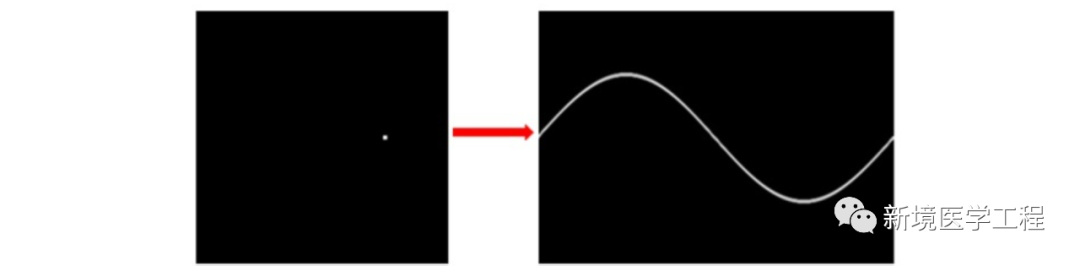

与常规X射线成像设备相比,CT系统本质上更容易产生伪影:一个CT图像是由大量投影生成的。在一个典型的CT系统中,每个投影包含大约1000个单独的测量,在多层CT的情形下,形成一幅图像需要使用10E19个独立信号读取或测量!由于反投影过程的本质是将投影中的一点映射到图像中一条直线(如下图),投影读数的一个误差不像常规射线照相的情况,不再局限于局部区域。因为测量的不准确通常表现为重建图像中的误差,所以CT产生伪影的概率明显偏高。